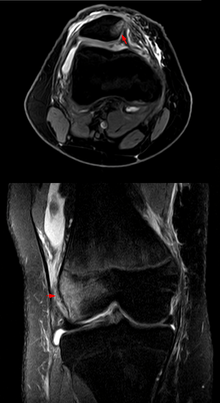

![]() | |